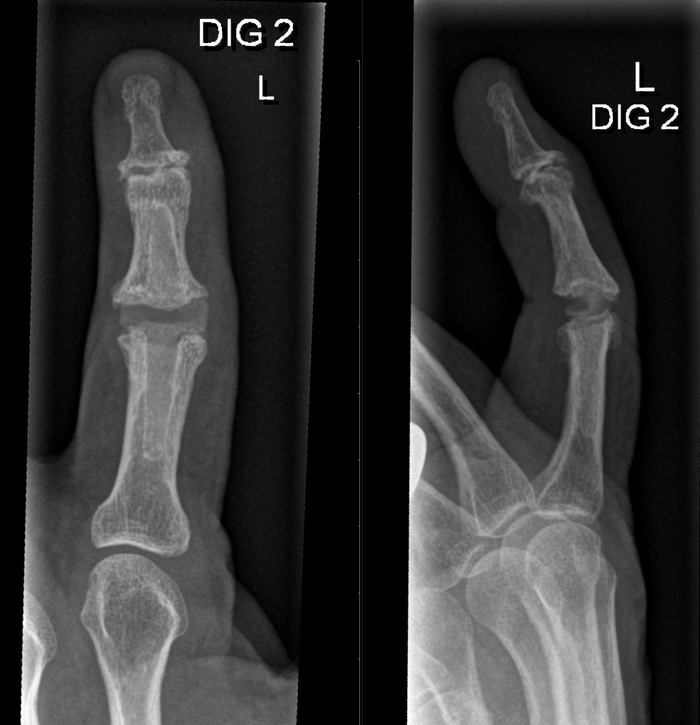

Перейдём к верхней конечности, где имплантируют протезы:

- межфалангового сустава (здесь уже нередко не металл, но синтетические материалы)